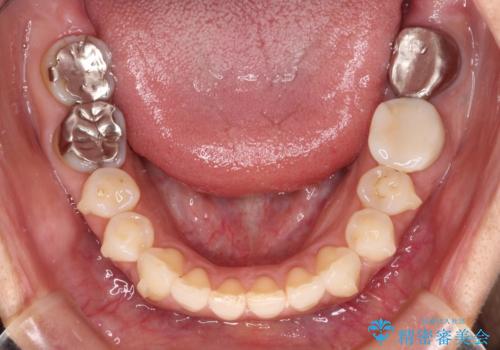

まずは左下奥歯の根管治療を行い、痛みが引いたことを確認してから矯正治療を開始しました。

後戻りは軽微であったため、インビザライン・ライトにて歯列を整えました。

矯正治療後には、左下奥歯の症状がないことを確認し、セラミッククラウンにて補綴治療を行うこととしました。